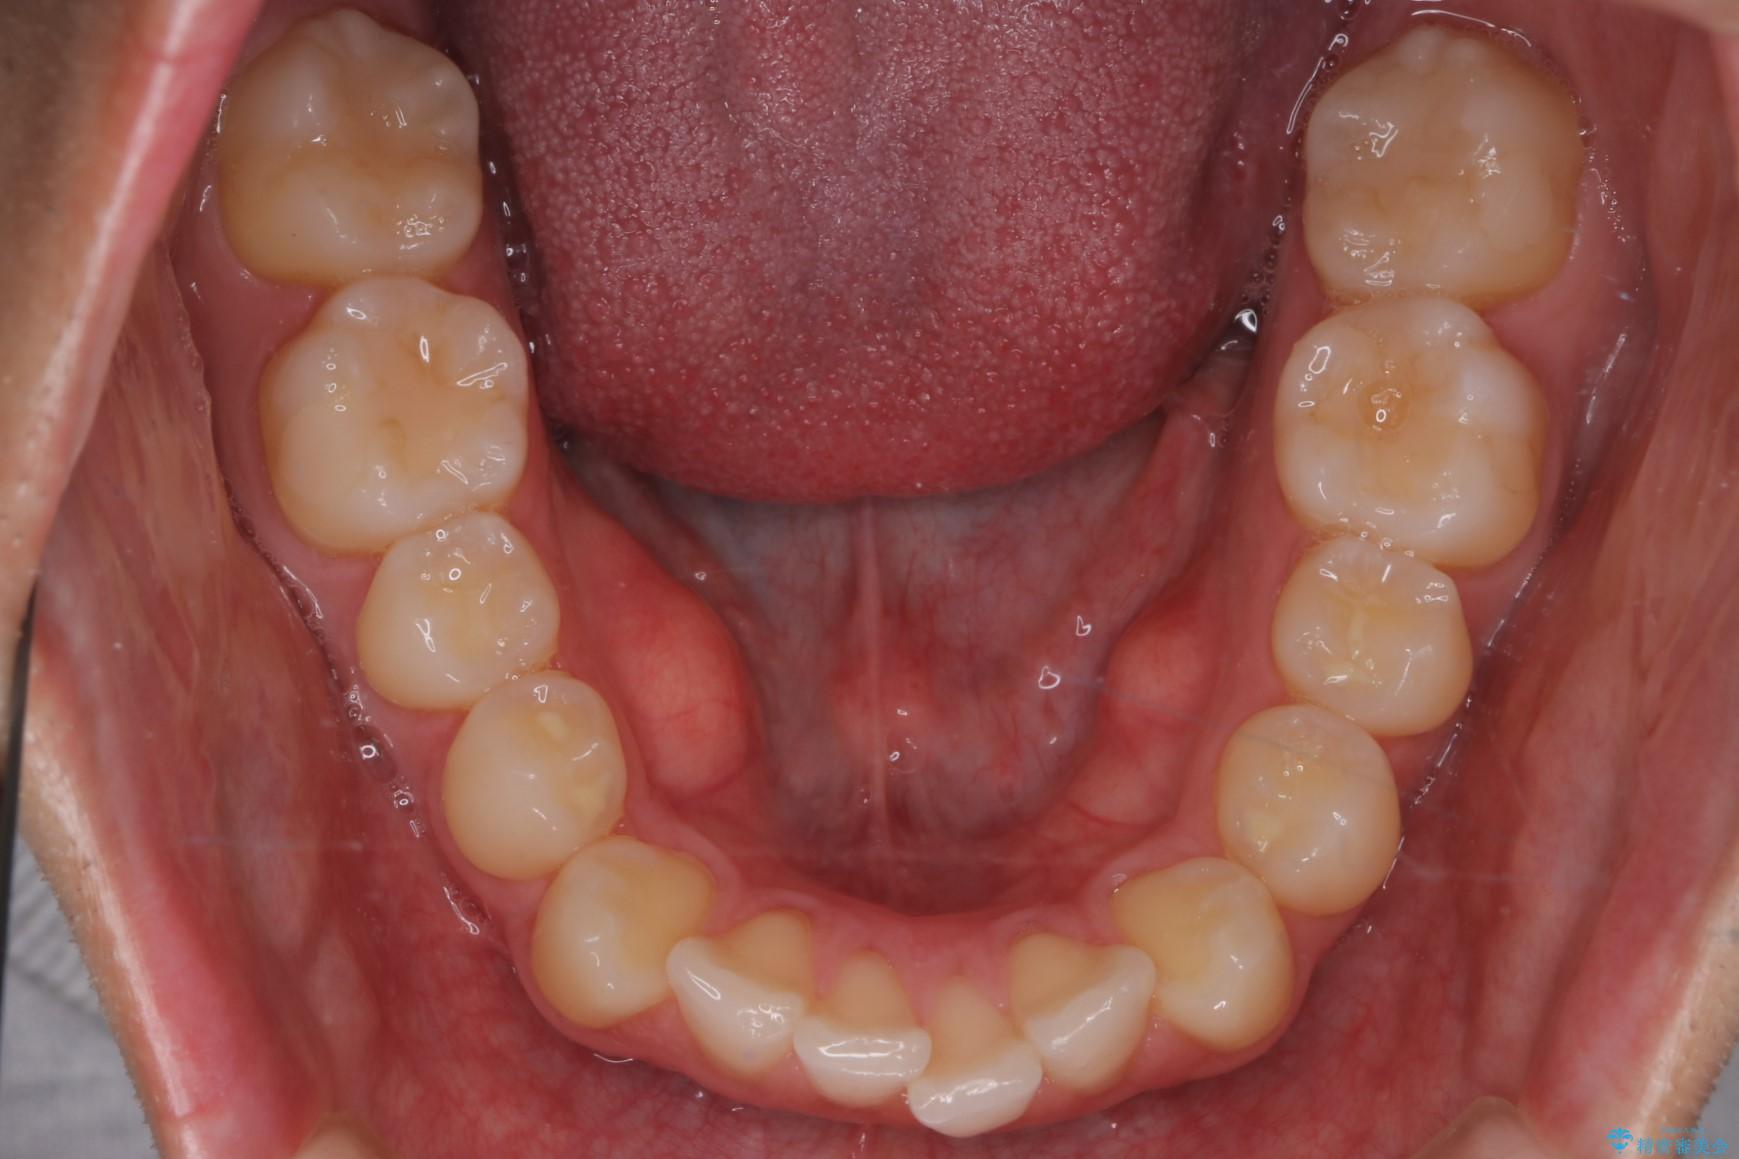

上の前歯が出ているのが気になるとご来院された患者様です。

IPR(歯と歯の間を削る処置)を行うことで、前歯の位置とがたつき整える治療計画を立てました。